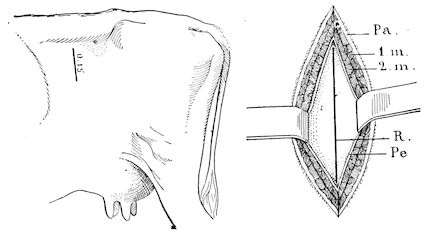

Fig. 10.—Dressing for fracture of the horn.

Symptoms. The symptoms are extremely simple. They consist mainly in the mobility of the fractured end, and such phenomena as sensitiveness, hæmorrhage, etc. When the fracture extends to the frontal bone, crepitation may also be noted.

Prognosis. The prognosis is not grave unless the fracture extends to the basilar half of the horn or affects the frontal bone.

Treatment. (1.) If the fracture is confined to the horn core, it is only necessary to bring the fragments into regular apposition, after having removed the broken end of the horn itself.

(2.) In treating a fracture affecting the middle portion of the horn or in treating animals destined for the butcher, the best method is to make a simple wound by dividing the parts with a saw below the fracture. This is a painful operation, necessitating anæsthesia, and requiring the animal to be cast or firmly fixed to a post or placed in a trevis. To diminish the painful stage of the operation, it was formerly recommended to make a circular incision extending through the entire thickness of the horn proper, and then to remove with a fine, very sharp saw the portion of the horn core. This, however, is scarcely practicable, and it is much better to make a direct section. Hæmorrhage is checked with compresses, moistened with cold water, after which a dressing known as the “Maltese cross dressing” (Fig. 10) is applied according to general principles.